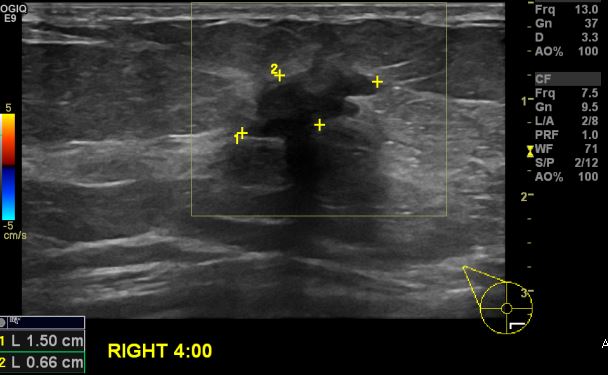

상기환자 우측 유방에 만져지는 멍울로 내원하신 50대 여성 분으로 우측 4시 방향에

만져지는 멍울 조직검사 시행하여 우측 침윤성 유관암 진단 되었습니다.